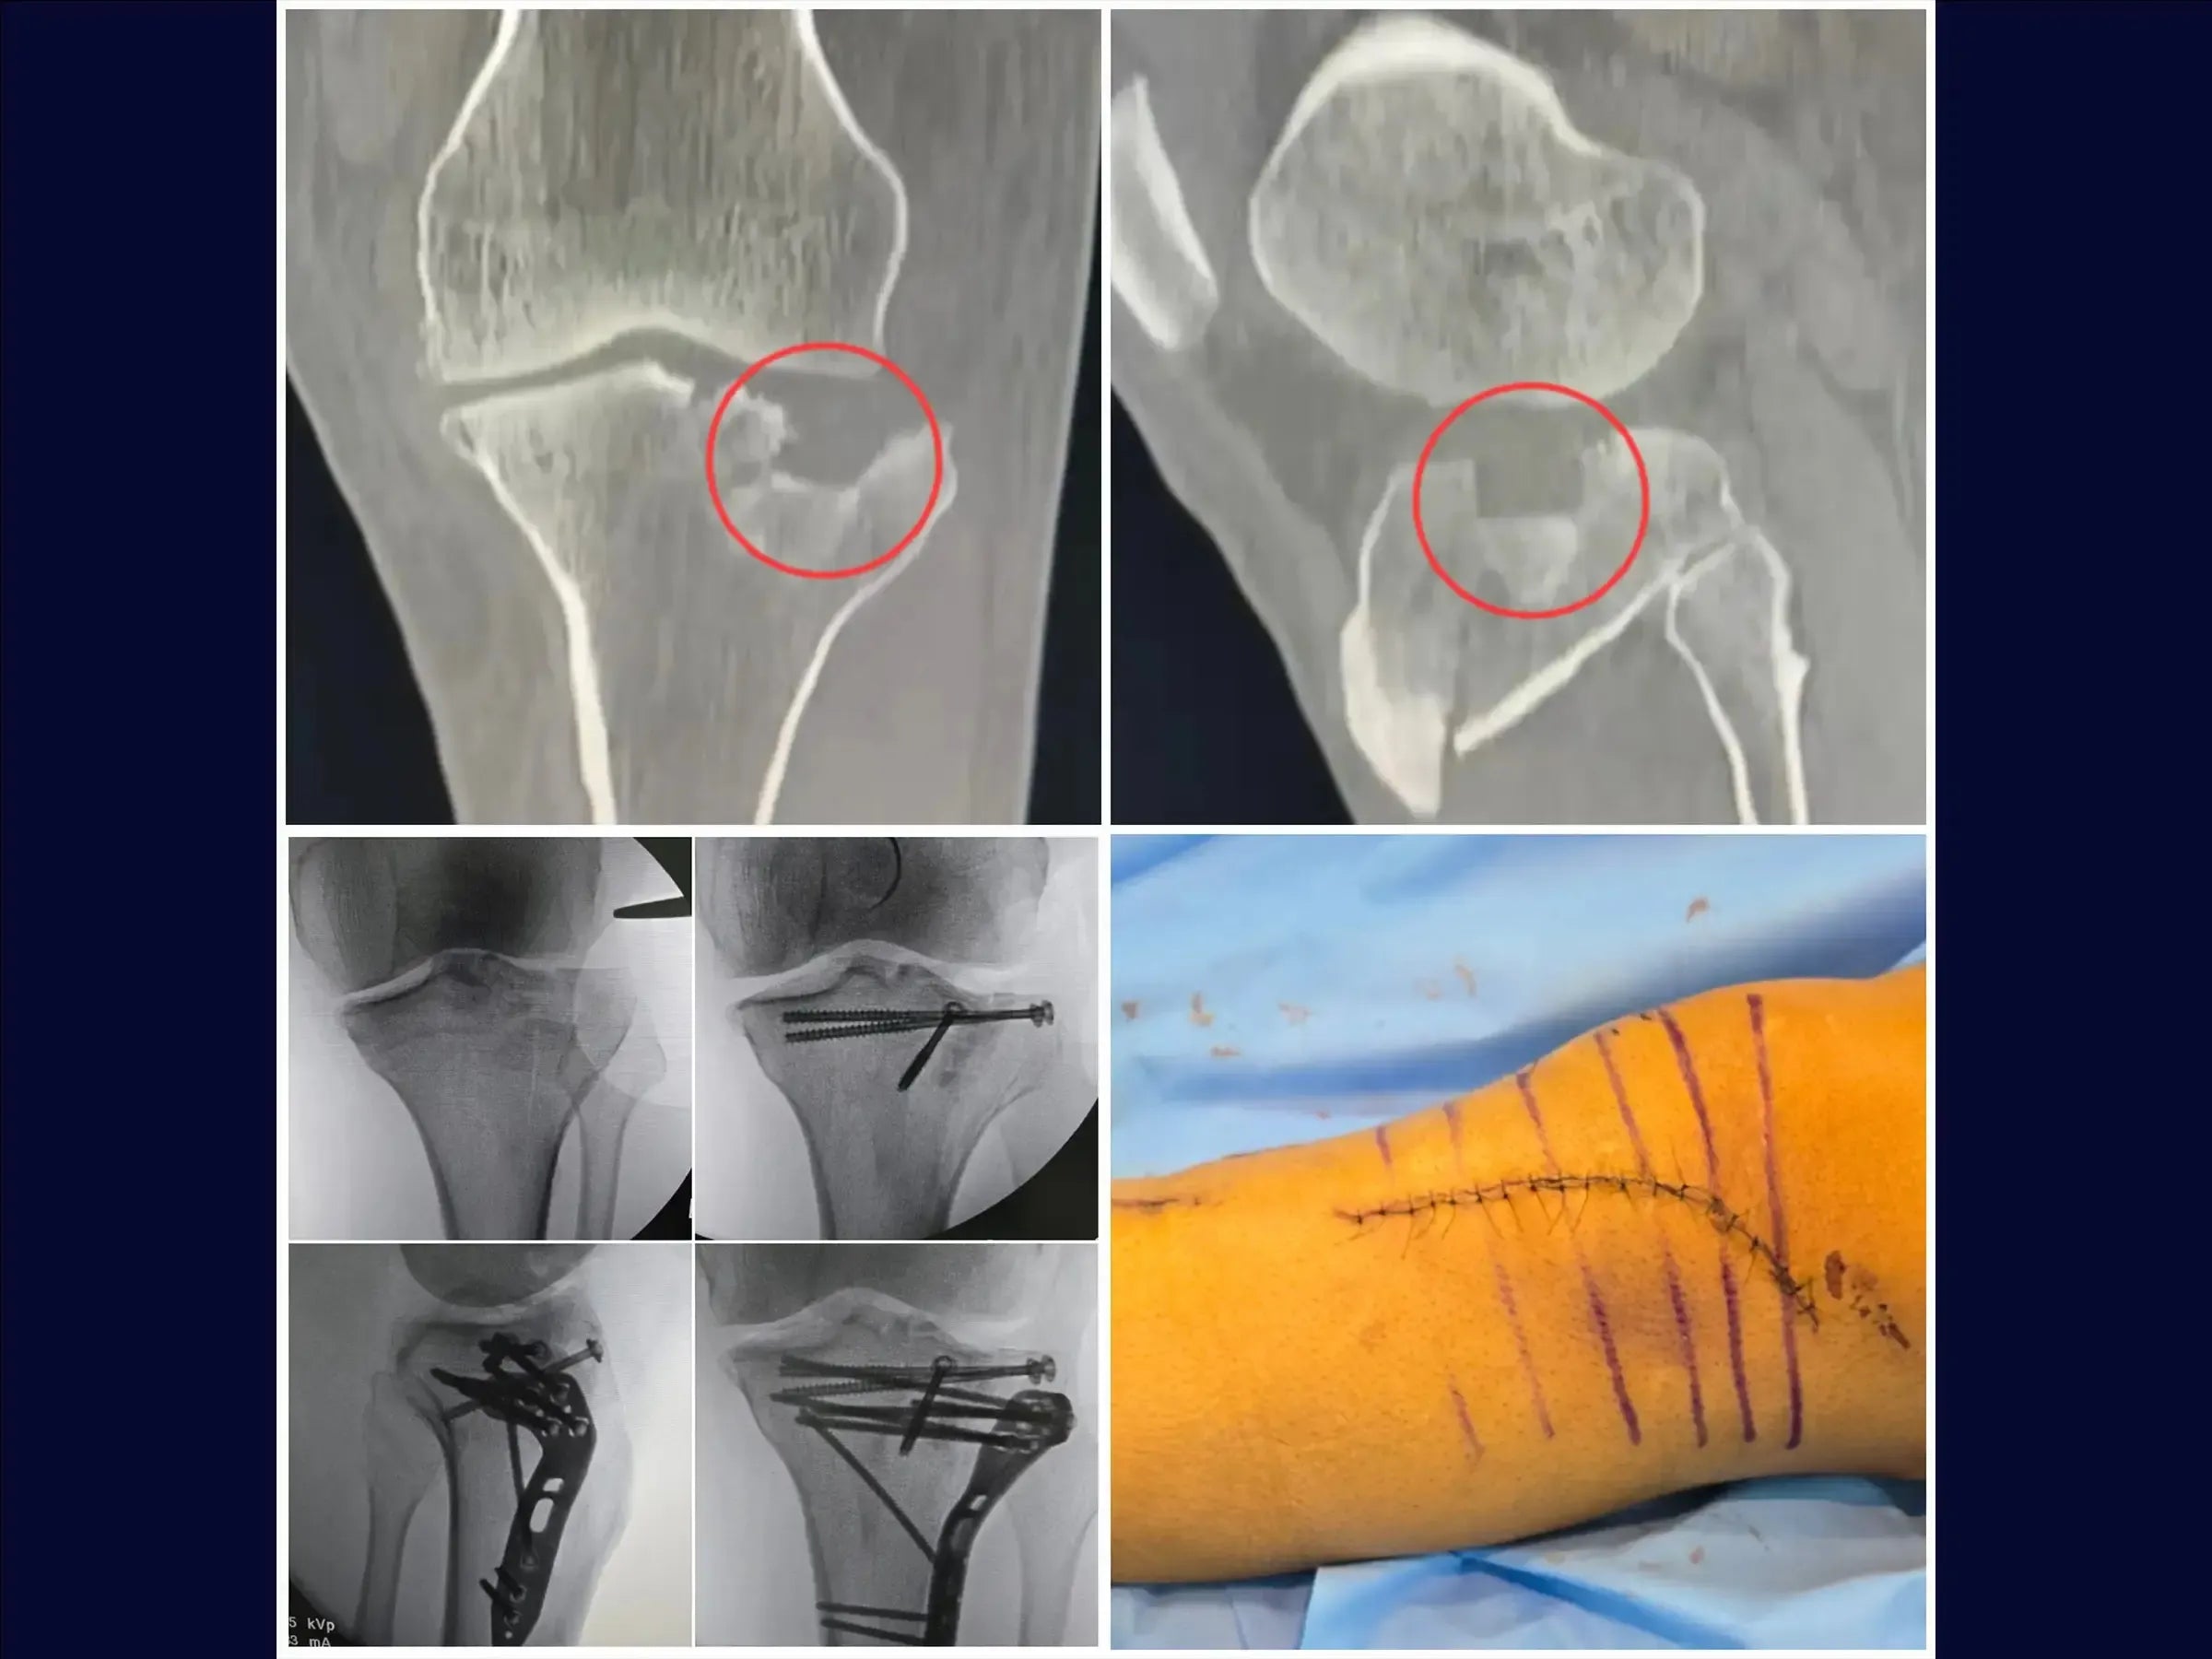

- Osteossíntese de fraturas do platô tibial com afundamento central e cisalhamento incompleto.

- Técnica de osteotomia incompleta (elástica) para levantamento de fragmentos afundados.

- Utilização de enxerto ósseo estrutural e fixação com parafusos canulados subcondrais e placa.

- Manejo do Menisco e Exposição Articular: Preparo do menisco com fios de Vicryl e levantamento preciso para ampla exposição do afundamento, garantindo a integridade das estruturas.

- Osteotomia Elástica para Redução Anatômica: Abordagem de osteotomia incompleta que mantém a cortical anterolateral íntegra, permitindo o levantamento do fragmento afundado com retorno natural à posição.

- Estratégias de Enxertia Óssea: Protocolos para preenchimento da depressão com enxerto em grânulos, incluindo hipercorreção para acomodação e resistência, e uso de enxerto estrutural para suporte.

- Fixação Estável e Rede Subcondral: Posicionamento de fios guia para parafusos canulados subcondrais, criando uma "rede" para estabilidade primária, e utilização estratégica da placa para compressão e manutenção do levantamento.

- Fechamento por Planos para Reestruturação: Abordagem sistemática para o fechamento de tecidos moles e ósseos, reestruturando a anatomia e otimizando o resultado funcional e estético.